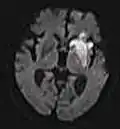

DWI showing necrosis (shown as brighter) in a cerebral infarction

DWI showing necrosis (shown as brighter) in a cerebral infarction -